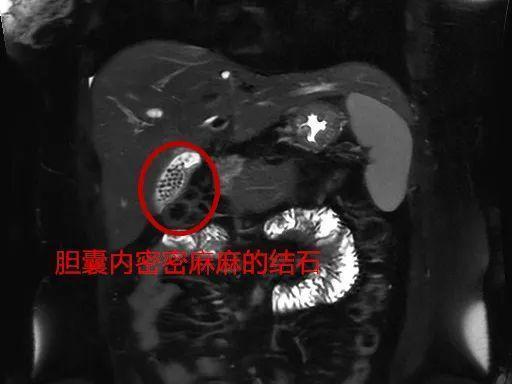

医生了解到,刘女士已婚已育,体型偏胖,平时喜欢喝奶茶、吃油腻的食物,检查发现刘女士的胆囊内竟然充满着大量结石。

手术过程中,外科团队将切除的胆囊打开一看,只见里面密密麻麻,满是形状不一、大小不规则的结石,足足有近百颗。